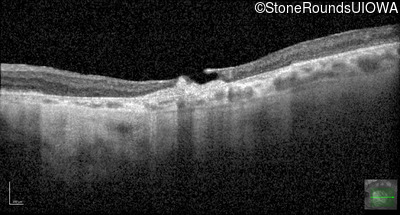

Optical Coherence Tomography - Left - 20/100

Exemplar / OCT Stack

OCT Stack